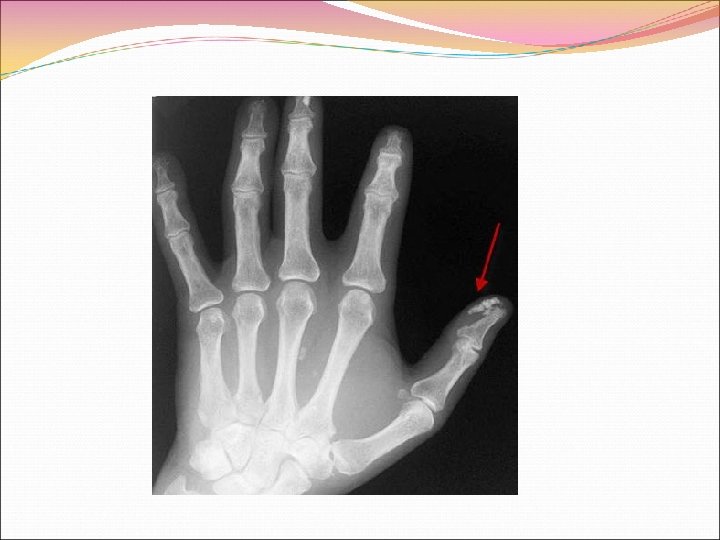

Поражение суставов при СКВ ограничивается артралгиями, симметричным неэрозивным артритом без деформации, анкилозов. Для волчаночного артрита характерны симметричные поражения мелких суставов кисти, коленных суставов, выраженная утренняя скованность. Может сформироваться синдром Жакку – артропатия со стойкими деформациями суставов за счет поражения сухожилий, связок, но без эрозивного артрита. В связи с васкулитом нередко развиваются асептические некрозы головок бедренной, плечевой, других костей

ЭКГ – признаки гипертрофии миокарда левого желудочка при сформировавшихся пороках (недостаточность митрального и / или аортального клапанов), артериальной гипертензии почечного генеза, разнообразные нарушения ритма и проводимости, ишемические нарушения. Рентгенография легких – выпот в плевральных полостях, очаговая инфильтрация (пневмонит), интерстициальные изменения (легочный васкулит), треугольные тени инфарктов при эмболиях ветвей легочной артерии. Рентгенография пораженных суставов – умеренно выраженный остеопороз без узурации, анкилозирования.

Рентгенологическое исследование: кальцинаты в тканях концевых фаланг пальцев, локтевых, коленных суставов; остеолиз дистальных фаланг пальцев кисти; остеопороз, сужение суставной щели, иногда анкилоз пораженных суставов. Грудная клетка – межплевральные спайки, базальный, диффузный, нередко кистозный (ячеистое легкое) пневмофиброз. ЭКГ: признаки миокардиодистрофии, ишемии, крупноочагового кардиосклероза с нарушениями проводимости, возбудимости, гипертрофии миокарда левых желудочка и предсердия при сформировавшейся недостаточности митрального клапана. Эхокардиография: верификация митрального порока, нарушений сократительной функции миокарда, дилятации камер сердца, могут выявляться признаки перикардита. Ультразвуковое исследование: выявление структурных признаков двустороннего диффузного поражения почек, характерного для нефрита, свидетельств аутоиммунного тиреоидита, фиброзной атрофии щитовидной железы, в отдельных случаях признаков билиарного цирроза печени.

Клинические критерии Американской ревматологической ассоциации для распознавания системной склеродермии (ACR, 1997): «Большие» критерии: Проксимальная склеродерма – двустороннее, симметричное утолщение, уплотнение, индурация, склероз дермы пальцев, кожи конечностей проксимально от пястно фаланговых и плюсне фаланговых суставов, вовлечение в патологический процесс кожных покровов лица, шеи, грудной клетки, живота. «Малые» критерии: Склеродактилия – индурация, склероз, остеолиз концевых фаланг, деформация пальцев кистей рук; Рубцы, дефекты тканей на подушечках пальцев кистей рук; Базальный легочный фиброз с двух сторон. Для диагноза СС у больного должны присутствовать либо «большой» , либо, по меньшей мере, два «малых» критерия.